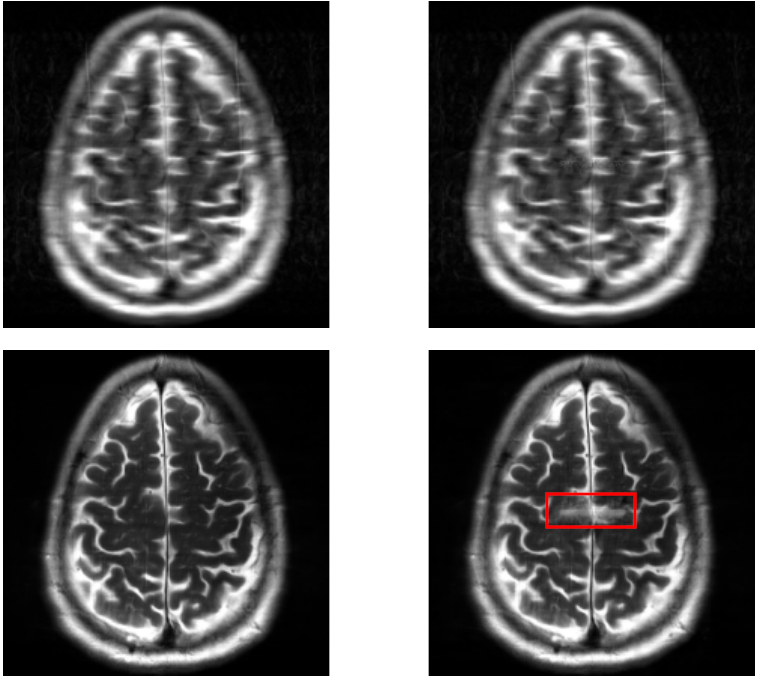

For a qualitative assessment of the results, we show some examples in figure˜0.B.1 for the UNet model and figure˜0.B.2 for the E2E-VarNet model of reconstructions where the attack was successful. These figures are structured as 2x2 panels of images where the first row displays the original and perturbed input samples and the second row displays the corresponding model-based reconstructions. Areas which we believe contain hallucinatory structures are highlighted in red.

We notice from LABEL:fig:unet-best1 and LABEL:fig:unet-best2 that the multi-coil images seem to be more vulnerable than the single-coil ones, in the sense that the resulting distortions are more severe for multi-coil data. The generated perturbations also seem easier to spot for single-coil data. This may be explained by the fact that perturbations in the multi-coil images can be more “spread out” across the coils, whereas with single-coil data this is not possible. This is consistent with the observation that vulnerability to adversarial examples increases with data dimensionality [14, 27]. Although we cannot compare to single-coil data for the E2E-VarNet, we do notice large distortions in LABEL:fig:varnet-best1 as well that go far beyond the boundaries of our inserted detail. On the multi-coil brain data, the hallucinations seem less severe for both models compared to the knee data, but the distortions can still be significant as they tend to resemble non-existent sulci. For knee images, the distortions appear to substantially change the structure of the knee joint, especially on multi-coil data.